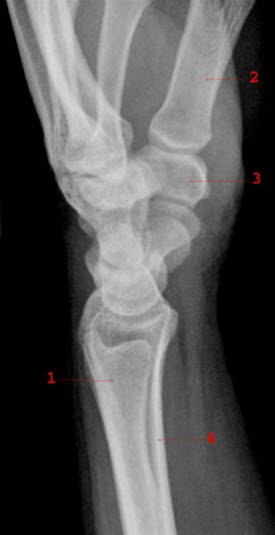

Normalt sidebilde av håndledd med håndrotsknokler

1. Ulna

2. 1. metakarp

3. Os trapezium

4. Radius